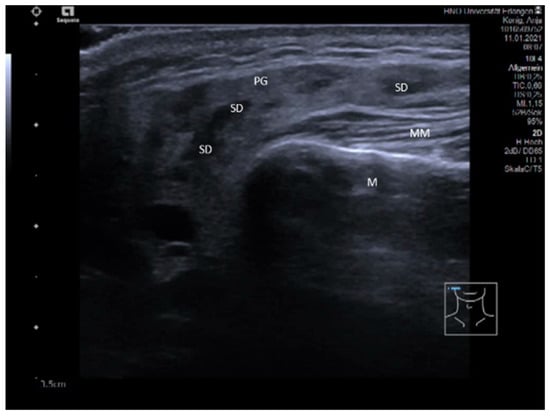

3.2. Findings in Normal Anatomy in Major Salivary Glands